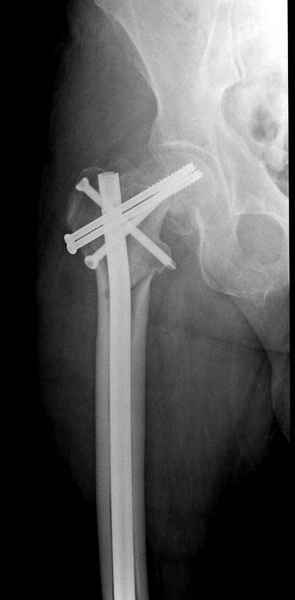

Правильно, ситуация изменилась, как говорят у нас теперь "different animal", надо решать проблему подвертельного перелома. При наличии различных вариантов фиксаторов, включая Страйкер Гамма 3, мы выбрали DePuy Antegrade Trachanteric Nail из-за многовариантности проксимальной фиксации и двойного изгиба. Вводится через вертел под 8 градусным углом, и есть достаточный передний диафизарный изгиб, предупреждающий пенетрацию дистального переднего кортекса.

Кто знает что дальше, мысленно готовы к проксимальной артропластике.